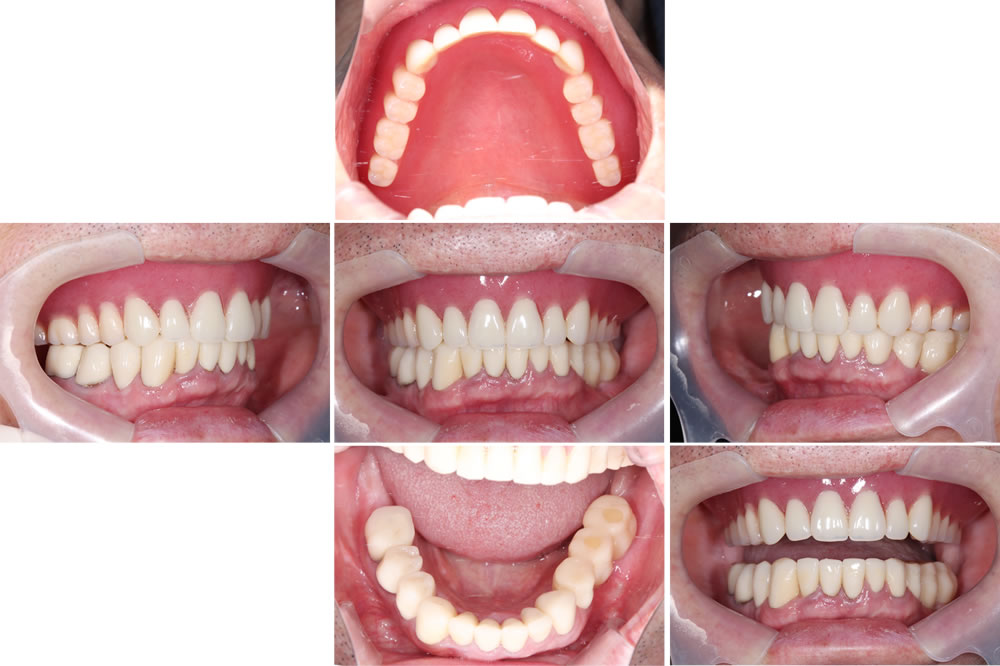

治療終了時の口腔内

下顎はインプラントおよびセラミックによる補綴治療を行い、上顎は保険適用の義歯を装着しています。

治療前後の比較

術前と比較して咬み合わせが安定しました。歯の傾斜も改善され、審美的にも患者さまにご満足いただけました。下顎は補綴前に必要部位の根管治療を行っています。X線写真上、下顎右4番の根尖病変は縮小傾向を示しています。